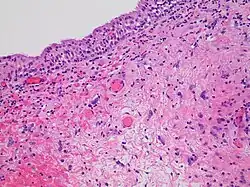

- Radiation necrosis

- Radiation necrosis is the death of healthy tissue near the irradiated site. It is a type of coagulative necrosis that occurs because the radiation directly or indirectly damages blood vessels in the area, which reduces the blood supply to the remaining healthy tissue, causing it to die by ischemia, similar to what happens in an ischemic stroke.[51] Because it is an indirect effect of the treatment, it occurs months to decades after radiation exposure.[51] Radiation necrosis most commonly presents as osteoradionecrosis, vaginal radionecrosis, soft tissue radionecrosis, or laryngeal radionecrosis.[5]